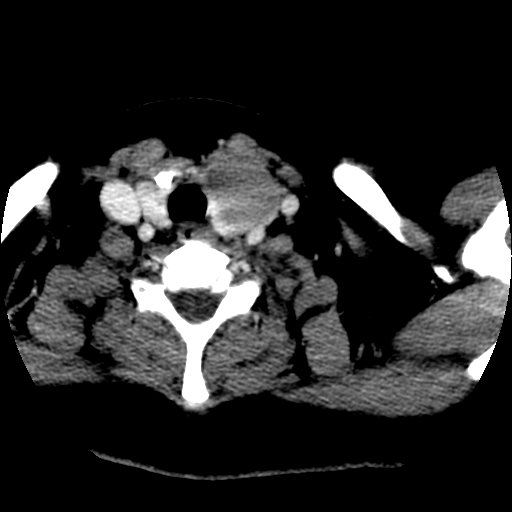

左右叶都有,峡部也受累,有钙化,考虑结甲可能性大。

考虑右叶结节性甲状腺肿,伴左叶钙化。主要(1)密度均匀,边境清。(2)病灶与血管界限清。

边界清,无明显强化,考虑考虑甲状腺腺瘤